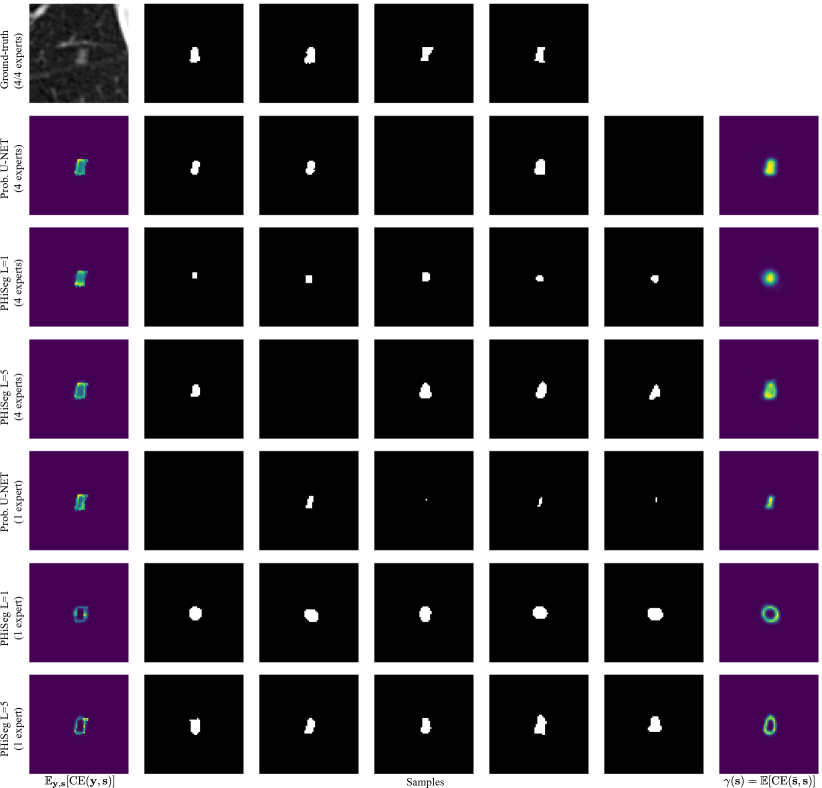

We evaluated the techniques in two experiments. First, we trained the methods using the masks from all available annotators, where in each batch we randomly sampled one annotation per image. We were interested in assessing how closely the distribution of generated samples matched the distribution of ground-truth annotations. To this end, we used the generalised energy distance where is 1 minus the intersection over union, i.e. , and are samples from the learned distribution , and ground-truth distribution [4]. The GED reduces the sample quality to a single, easy-to-understand number but, as a consequence, cannot be interpreted visually. Therefore, we additionally aimed to produce pixel-wise maps showing variability among the segmentation samples. We found the expected cross entropy between the mean segmentation mask and the samples to be a good measure, i.e. with the pixel position and the mean prediction. is statistically similar to variance with the L2-distance replaced by CE. However, we believe it is more suitable for measuring segmentation variability. Examples of our -maps along with sample segmentations are shown in Fig. 3. We quantify how well the -maps for each method predict regions with large uncertainty using the average normalised cross correlation (NCC) between the -maps and the CE error maps obtained with respect to each annotator:

We observed that when using all annotators for training, PHiSeg () produced significantly better and scores compared to all other methods. This can be observed qualitatively in Fig. 3 for a prostate slice with large inter-expert disagreements. Both, the prob. U-NET and PHiSeg () produced realistic samples but PHiSeg () was able to capture a wider variability. Furthermore, as indicated by the high values, PHiSeg’s () -maps were found to be very predictive of where in the image the method’s average prediction errors will occur. Similar results were obtained when training with only one annotator. We noticed that in this scenario the prob. U-NET may in some cases fail to learn variation in the data and revert back to an almost entirely deterministic behaviour (see fourth row in Fig. 3). We believe this can be explained by the prob. U-NET’s architecture which, in contrast to our method, allows the encoder-decoder structure to bypass the stochasticity. While our method also predicted smaller variations in the samples, they were still markedly more diverse. The lower performance of PhiSeg () indicates that using multiple resolution levels is crucial for our method. More samples for the prostate and LIDC-IDRI datasets can be found in Appendix B. From Tab. 1 it can be seen that no significant differences between the Dice scores were found for any of the methods (except PHiSeg’s ()), including the det. U-NET. From this we conclude that neither PhiSeg () nor the prob. U-NET suffer in segmentation performance due to their stochastic elements.

Appendix 0.B Additional Samples

Fig. 0.B.2 shows a thoracic lesion with disagreements regarding the shape of the lesion, while Fig. 0.B.3 is showing an example where the disagreement is over presence or absence of the lesion.